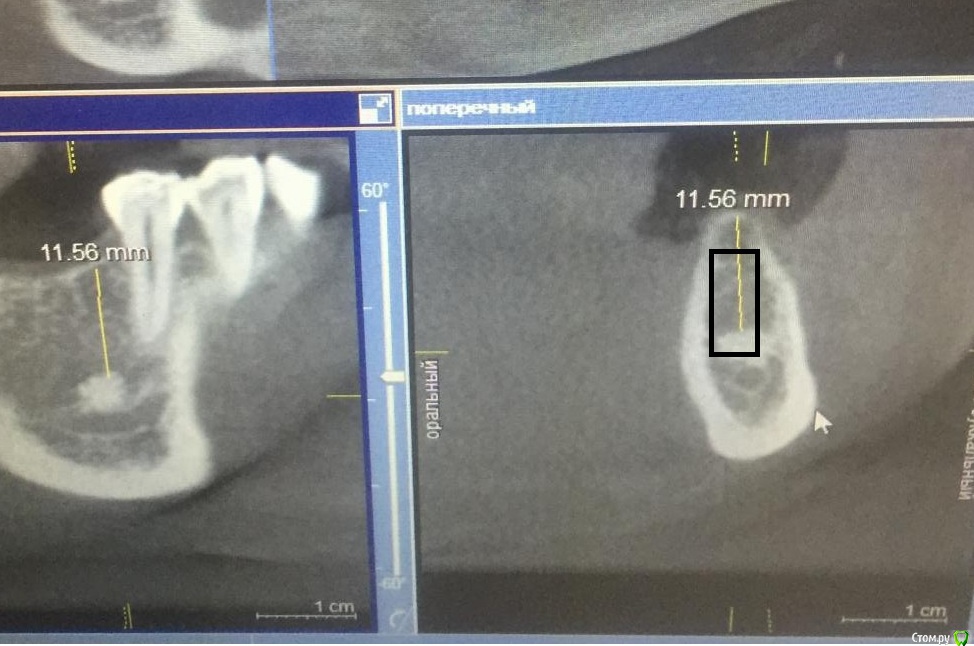

pavlin Опубликовано 27 июня, 2017 Поделиться Опубликовано 27 июня, 2017 Решили ставить имплант в обл 46. Зуб удалялся более 15 лет назад. После снимка обнаружили в обл 46 новообразование костного типа. Коллеги нужен совет. Можно ли в данном случае ставить Имплант? Образование 4,5*3мм, до него 11,5 мм. Ставить 10мм Имплант? Или ставить рядом? Или выбрать другую методику восстановления зубного ряда? Заранее благодарю Ссылка на комментарий

АнтонТЛТ Опубликовано 27 июня, 2017 Поделиться Опубликовано 27 июня, 2017 Можно хоть 10мм, хоть прям в остеому 1 Ссылка на комментарий

Aquarius Опубликовано 28 июня, 2017 Поделиться Опубликовано 28 июня, 2017 А что с шириной гребня ? по остеоме - хоть в нее, хоть не доходя до нее. Ссылка на комментарий

pavlin Опубликовано 28 июня, 2017 Автор Поделиться Опубликовано 28 июня, 2017 А что с шириной гребня ? по остеоме - хоть в нее, хоть не доходя до нее. По ширине 3,5мм будем делать одномоментно с графтом и мембраной. Просто испугался новообразования , коллега сказал , что это противопоказание к имплантации, вот и возник вопрос Ссылка на комментарий